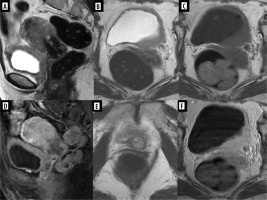

Figure 1

A 66-year-old woman with gastric carcinoma (poorly cohesive ca) after total gastrectomy with lymphadenectomy, postoperative chemoradiotherapy with 45 Gy radical radiotherapy to the gastric area and regional lymph nodes. Follow-up magnetic resonance imaging – Krukenberg tumours (arrows) confirmed after surgery: within the ovaries metastases of signet ring cell gastric cancer. Upper row: inhomogeneous abnormal ovaries on T2-weighted image (T2WI) (A), STIR (B) with inhomogeneous diffusion restriction (C). T1WI before (D) and after contrast medium administration (E, F) – very inhomogeneous contrast enhancement of the affected ovaries

Figure 2

A 52-year-old woman with the absurd suspicion of adenomyosis, put forward after ultrasound. Multiple tumours in the uterine body and cervix as well as in both ovaries. After surgery: synchronous G1 endometrioid carcinoma of the uterus and ovaries, most likely on the basis of endometriosis. The arrows point at the smaller lesion in the left ovary. A, B) T2WI, C) STIR, D-F) post-contrast T1WI

Figure 3

A 71-year-old woman with a diagnosis of endometrial carcinoma (A-D). Magnetic resonance imaging shows the additional findings: metastasis to the vagina (A, D-F, arrows) and to the right ovary (B, C). A, B, E) T2WI, C, D, F) post-contrast T1WI

Figure 4

A 54-year-old woman with adenocarcinoma of the left lung with known metastases in both lungs and adrenal glands. Magnetic resonance imaging (MRI) showed metastases to the uterine corpus (as a whole) and focally to the cervix (A, D), to the vagina on the left side (B, C, F), to the urinary bladder on the left side (A-D, F), and to the urethra (E). Bone metastases were also depicted on pelvic MRI (not shown here). A, B, E) T2WI, C) T1WI, D, F) post-contrast T1WI